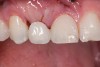

Fig 22. Right lateral view.

Figure 22